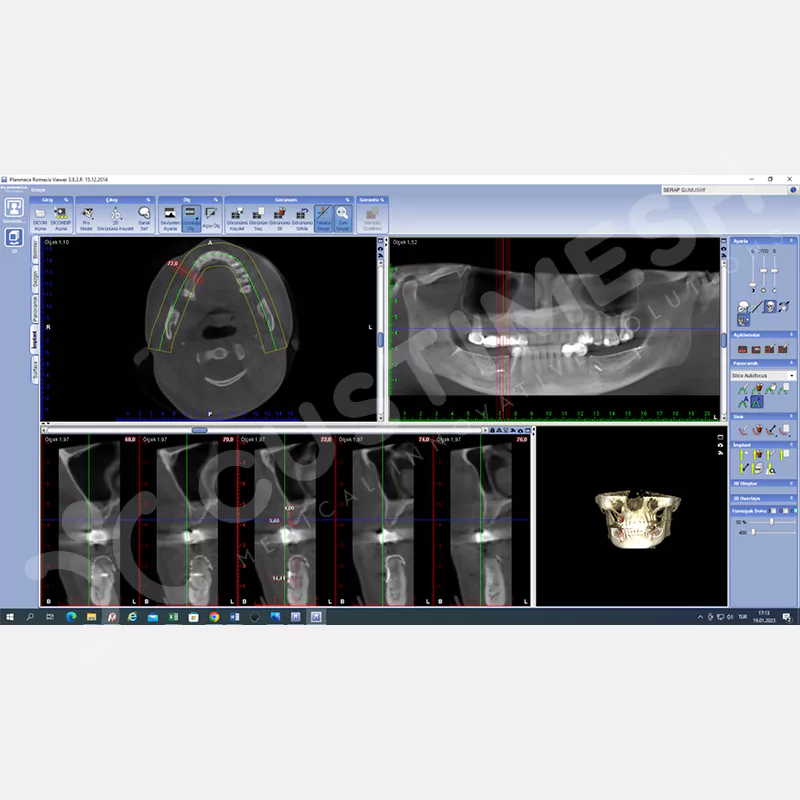

- DICOM

Hastanın DICOM dosyası WeTransfer aracılığıyla custimesh.case@gmail.com adresine gönderilmelidir. *AÇIKLAMA kısmına hekim adı ve Custiplate yapılacak ilgili bölge belirtilmelidir. Custiplate için, Fov genişliği tedavinin uygulanacağı bölgeyi kapsayacak şekilde 0.5 mm kesit kalınlığında Medikal CT çekilmelidir. - HEKİM ONAYI

Custiplate planlanacak bölge dikkate alınarak 3 boyutlu model hazırlanır, hekimin onayına sunulur ve gerekli değerlendirme için hekimle iletişim sağlanır. - ÖDEME

İlgili bölge için ön değerlendirmeler ve analizler yapılıp Custiplate’in tasarımı

bitirilir. - HEKİM ONAYI